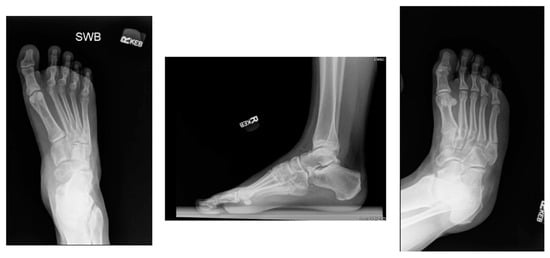

3.2. Diagnosis

3.3. Treatment Considerations